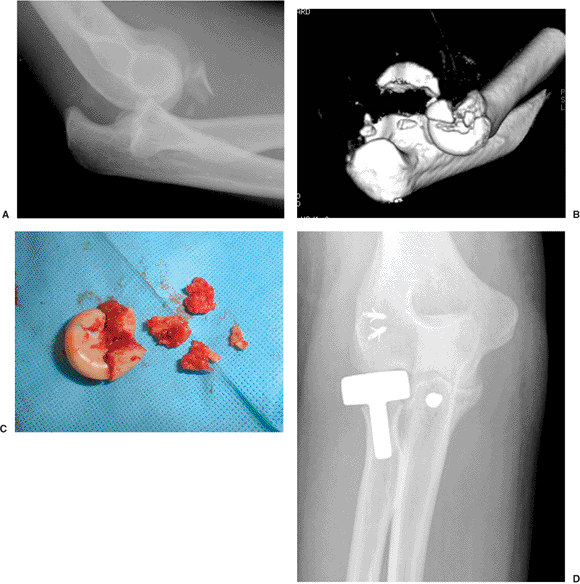

![]() |

|

Figure 9.2. CT can help characterize a fracture of the radial head. A.

This radiograph of a terrible triad fracture-dislocation suggests that the radial head fracture is partial and relatively small. B. A CT scan demonstrates that at least one half of the radial head is involved and the fracture has created complex comminution. C. The fragments were not repairable. D. Because this portion of the radial head is critical to stability in the setting of a terrible triad injury, a metal prosthesis was used with a good result. (Copyright © David Ring, MD.) |